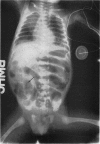

Images in this article